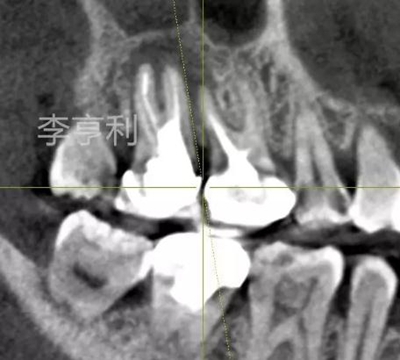

【輔助檢查】: CBCT見17冠部大面積充填物阻射影,接近髓室底,根管內(nèi)充填物錐度尚可,距根尖均為2mm以內(nèi),根尖周大范圍阻射影主要在頰根區(qū)域,波及16的DB根尖區(qū)域,頰腭側(cè)骨板完整

【術(shù)前診斷】: 17已行根管治療,急性根尖膿腫 (previously treated with acute apical abscess)